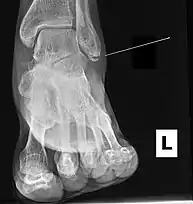

Ankle radiographs are used to detect widening of the tibiofibular syndesmosis or medial clear space. The medial clear space is the area between the talus of the ankle and the medial malleolus. Damage to the deltoid ligament and syndesmotic ligaments result in mortise instability, causing the talus to laterally shift and widen the medial clear space.[4][12] A clinical study, conducted in 2006 and published in the Journal of Bone and Joint Surgery, found that the medial clear space size of a normal ankle and an injured ankle measured at 4 millimetres and 5.4 millimetres in length respectively.[11] To confirm diagnosis, full-leg radiographs are used to inspect for fractures of the proximal fibula and widening of the interosseous clear space (or tibiofibular clear space). The interosseous clear space is the area between the medial side of the fibula and lateral side of the tibia. A peer-reviewed study, published in Injury in 2004, found that an interosseous clear space greater than 10 millimetres indicates diastasis of the syndesmotic ligaments.[4]

If necessary, Computed Tomography (CT) or Magnetic Resonance Imaging (MRI) may also be used to clarify diagnosis. MRI scans can check for interosseous membrane or tibial tubercle damage if high instability of the ankle is diagnosed.[8][11] Arthroscopy may be used to diagnose a syndesmotic lesion but is often not recommended due to operative difficulty.[13] Stress radiographs of the ankle are used to assess the integrity of the deltoid ligament and tibiofibular syndesmosis.[9][13] The size of the medial clear space can also be measured using stress radiography.[11]